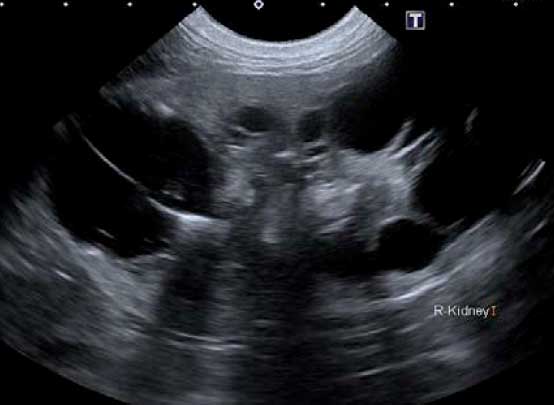

超音波検査

腎臓や膀胱の内部構造を確認します。腎臓においては形態や構造の変化、血流の評価を、膀胱においては壁の厚さや不整、内部の結石や血餅などの評価を行います。その他にも、尿管や尿道、雌では子宮や卵巣、雄は前立腺の評価にも有用です。

超音波腎臓

超音波膀胱